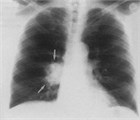

1. 肺がんの危険因子が多い患者では無症状でも胸部CTなど詳細な陰影の質的な評価と単純X線写真でとらえられないその他の異常所見の確認もする(推奨度1)

1. 肺がんの危険因子の乏しい患者での3cm以下の石灰化を伴う結節影は良性のことが多い(推奨度1)

1. 迅速に出現した結節影は円形肺炎を考える(推奨度1)